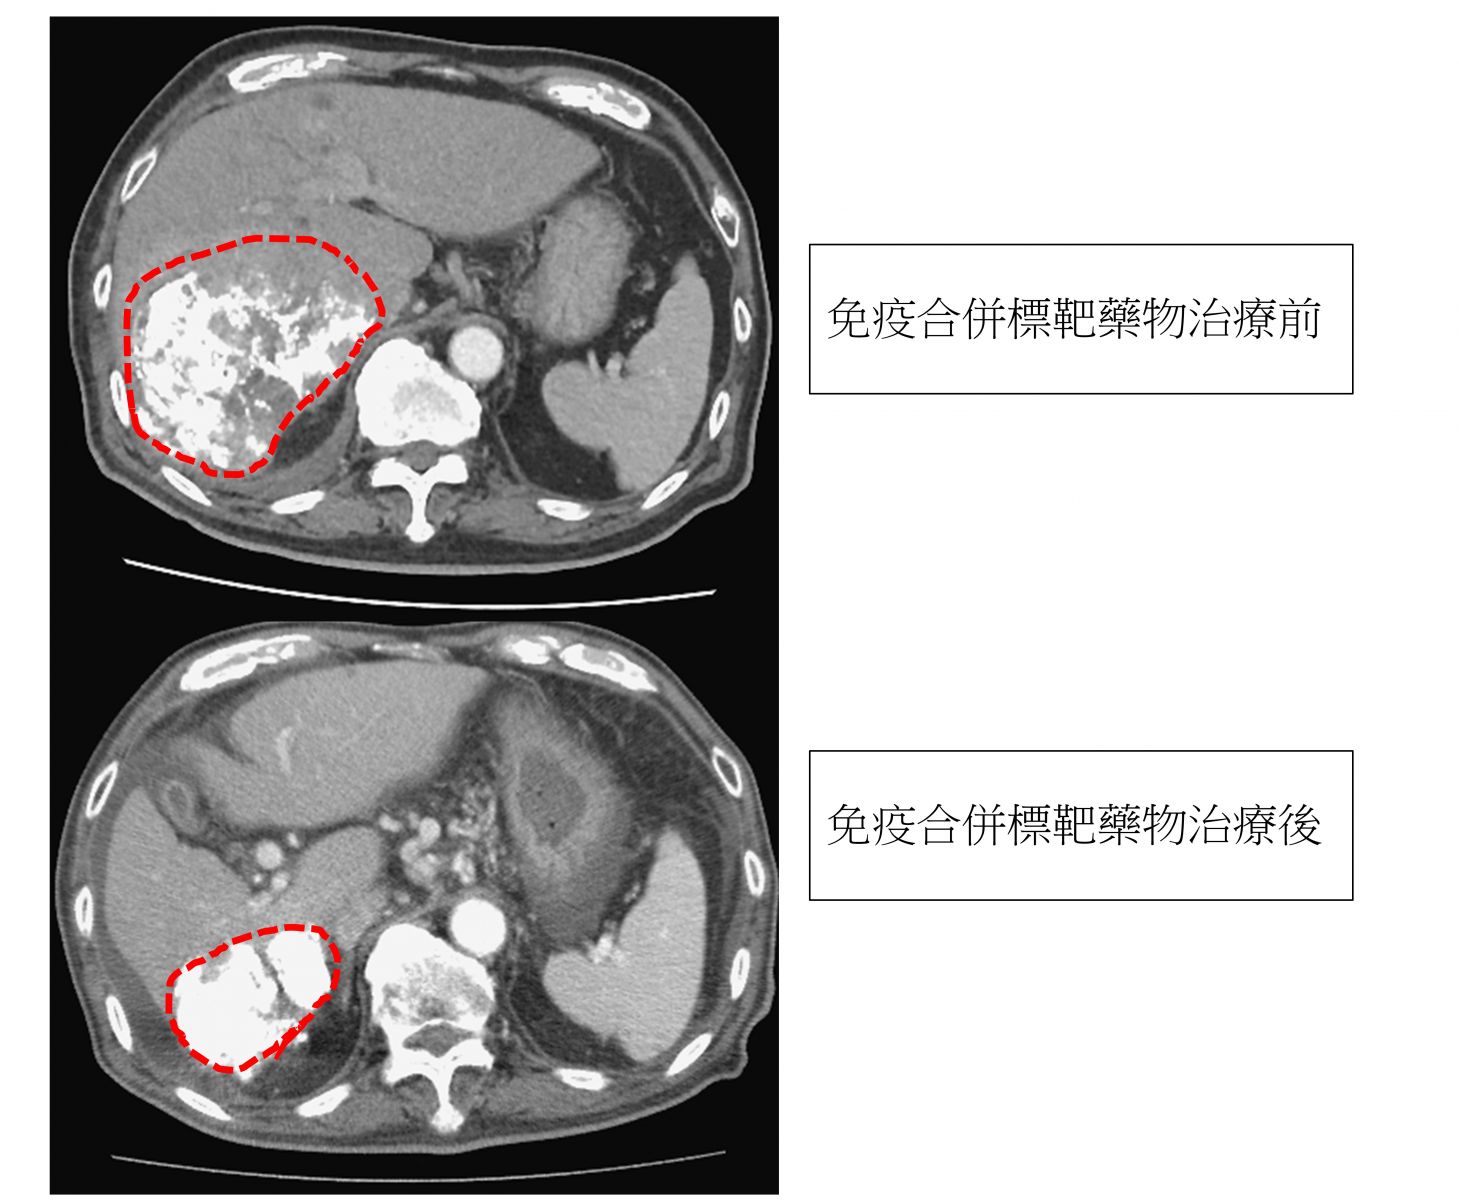

圖:免疫合併標靶藥物治療後,肝腫瘤由9公分縮小至4公分/台北榮總提供。

一名八十五歲的老先生罹患多發性肝腫瘤,最大的肝腫瘤達九公分,初次肝動脈化學栓塞效果不佳,考慮肝動脈栓塞的副作用,王老先生選擇免疫合併標靶藥物治療;治療後腫瘤成功縮小至4公分,體能維持良好。

胃腸肝膽科李懿宬醫師建議,最大顆的肝腫瘤公分數和腫瘤總數相加超過11的中期肝癌病人,應考慮其他的治療方式,近年來國際研究已證實好幾種標靶和免疫治療可以有效控制肝癌。以這位85歲患者為例,肝動脈栓塞化學療法對9公分且多顆的大腫瘤控制效果不佳,還必須面對肝衰竭的風險。因此患者在一開始接受不同的治療方式,治療過程副作用輕微,而且結果令人滿意。嚴重中期肝癌的病患,可以尋求藥物治療的方式,不僅可減少對肝臟的傷害,還可以達到更好的腫瘤控制。